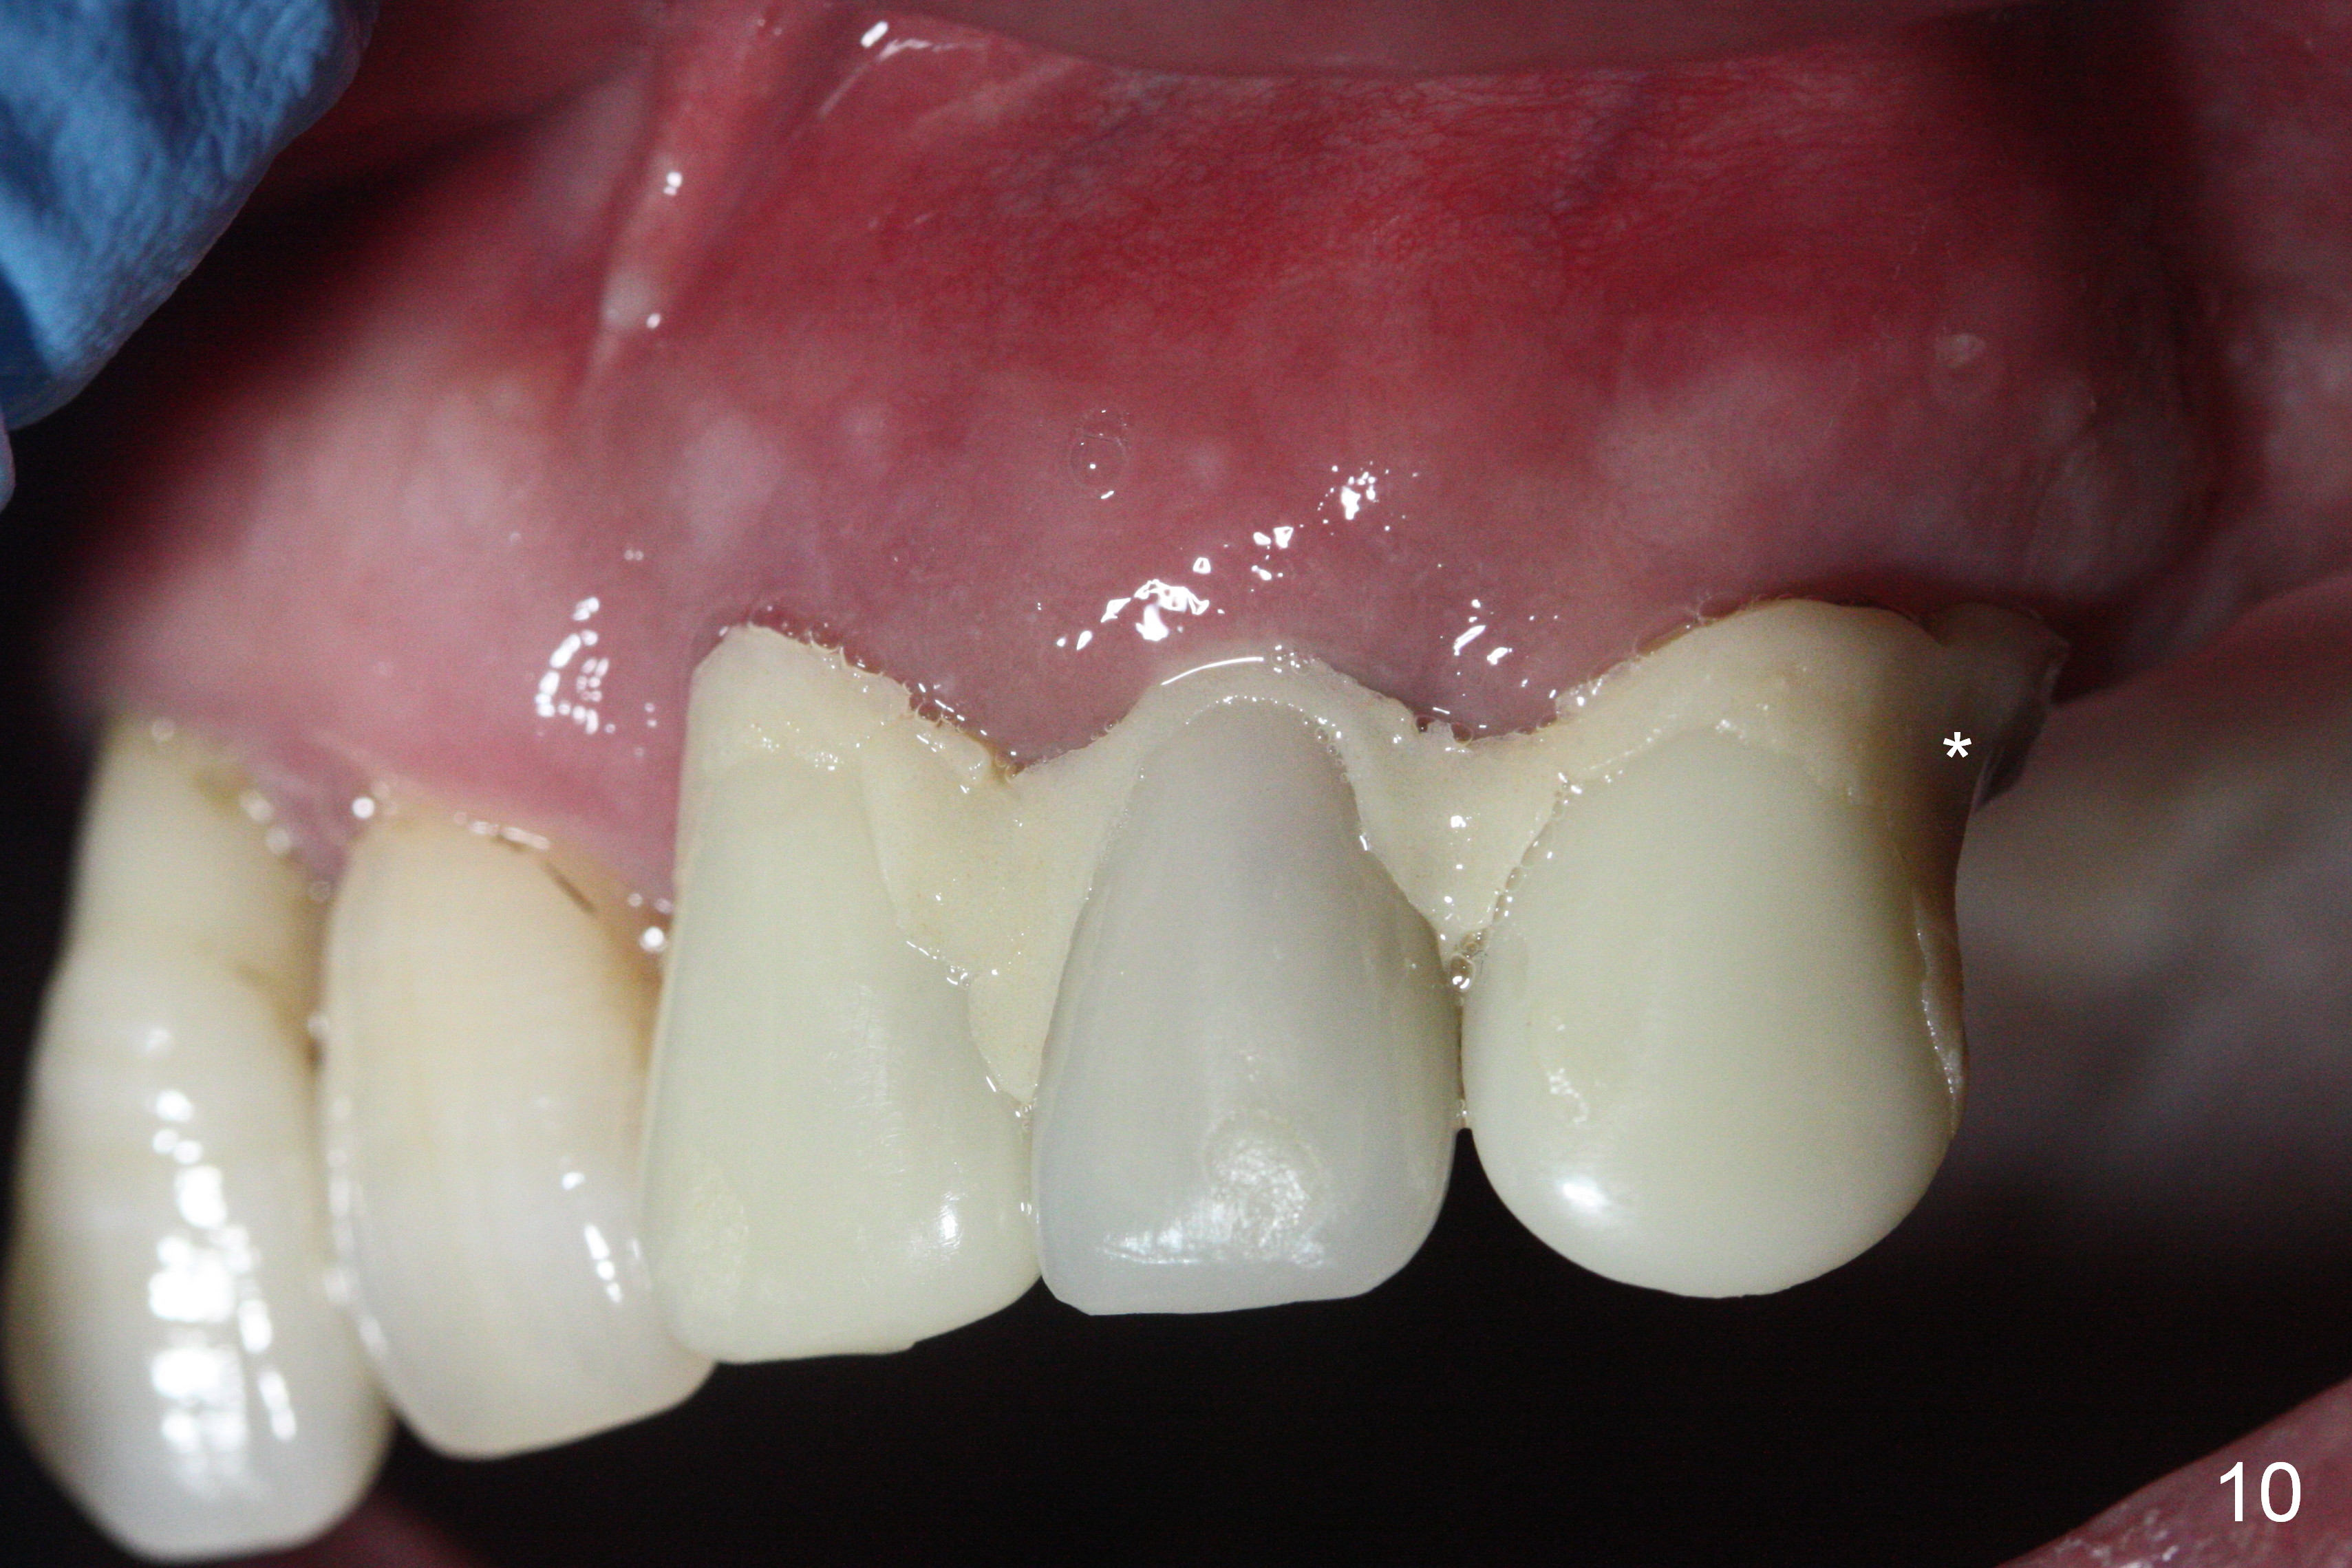

The patient returns 8 days postop, uncomfortable with overhang in the provisional (Fig.10 *). The sockets appear to be healing with loose bone graft (Fig.11) when the provisional is removed for trimming (Fig.12). Six (for #7,13) and seven (#9-11,15) months postop, the soft (Fig.13,17) and hard (Fig.14-16,18) tissues heal. It appears that the trajectory at #9,11 and 13 should be changed by using angled abutments (Fig.18,19 (panoramic X-ray taken 2 months earlier)) before provisional and final restoration.